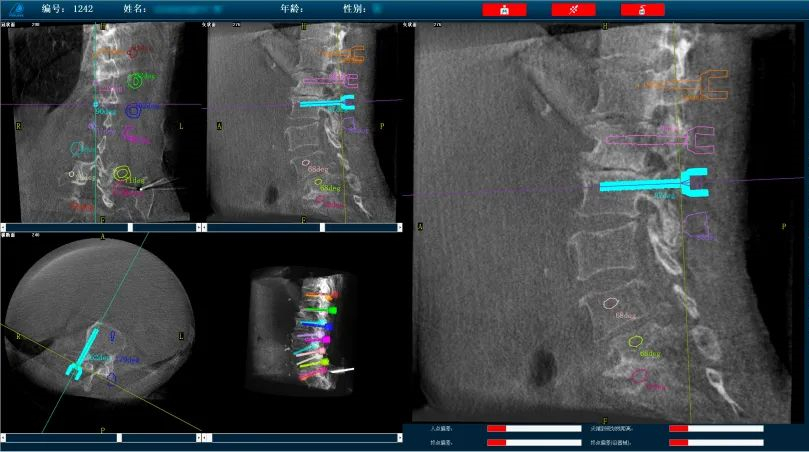

而外科手術(shù)機(jī)器人與三維C形臂配合,基于3D影像數(shù)據(jù),利用手術(shù)規(guī)劃軟件,術(shù)前模擬植入物狀態(tài),引導(dǎo)醫(yī)生進(jìn)行預(yù)手術(shù)規(guī)劃,輔助評(píng)估和及時(shí)調(diào)整手術(shù)路徑規(guī)劃設(shè)計(jì),機(jī)械臂準(zhǔn)確運(yùn)動(dòng)到規(guī)劃位置,借助導(dǎo)向套筒,為醫(yī)生提供穩(wěn)定的導(dǎo)針置入路徑。外科手術(shù)機(jī)器人以實(shí)現(xiàn)準(zhǔn)確、微創(chuàng)手術(shù)為首要目標(biāo),通過(guò)手術(shù)機(jī)器人準(zhǔn)確定位可以減小患者手術(shù)過(guò)程中的開口大小,減少神經(jīng)損傷風(fēng)險(xiǎn),實(shí)現(xiàn)手術(shù)操作的準(zhǔn)確度和安全性。

普愛醫(yī)療骨科手術(shù)機(jī)器人可廣泛地應(yīng)用于多節(jié)段脊柱外科手術(shù),輔助醫(yī)生定位病灶部位,為脊柱外科手術(shù)(經(jīng)皮椎體成形術(shù)、椎弓根螺釘內(nèi)固定術(shù)等術(shù)式))提供術(shù)前手術(shù)流程規(guī)劃、入釘位置、角度可視化引導(dǎo),模擬仿真入釘輔助。產(chǎn)品優(yōu)勢(shì)特點(diǎn)如下:

外科手術(shù)機(jī)器人配備高精度光學(xué)追蹤系統(tǒng)和機(jī)械臂,可基于3D影像數(shù)據(jù),利用手術(shù)規(guī)劃軟件,引導(dǎo)醫(yī)生進(jìn)行預(yù)手術(shù)規(guī)劃,輔助準(zhǔn)確定位植入物或手術(shù)器械,精度可達(dá)亞毫米級(jí)。尤其對(duì)高風(fēng)險(xiǎn)、復(fù)雜程度高的手術(shù)具有明顯優(yōu)勢(shì),可有效降低手術(shù)風(fēng)險(xiǎn)。

操作流程簡(jiǎn)單化:多次手動(dòng)入釘定位,操作繁瑣,骨科手術(shù)機(jī)器人可以實(shí)現(xiàn)多枚螺釘路徑一次性規(guī)劃,節(jié)省規(guī)劃定位時(shí)間,簡(jiǎn)化手術(shù)操作流程,提高置釘效率。

復(fù)雜手術(shù)標(biāo)準(zhǔn)化:直觀的軟件操作界面引導(dǎo),減少手術(shù)中的不確定環(huán)節(jié),使得復(fù)雜手術(shù)流程標(biāo)準(zhǔn)化,讓從業(yè)經(jīng)驗(yàn)不足的醫(yī)生也能快速掌握,縮短醫(yī)生的學(xué)習(xí)曲線。